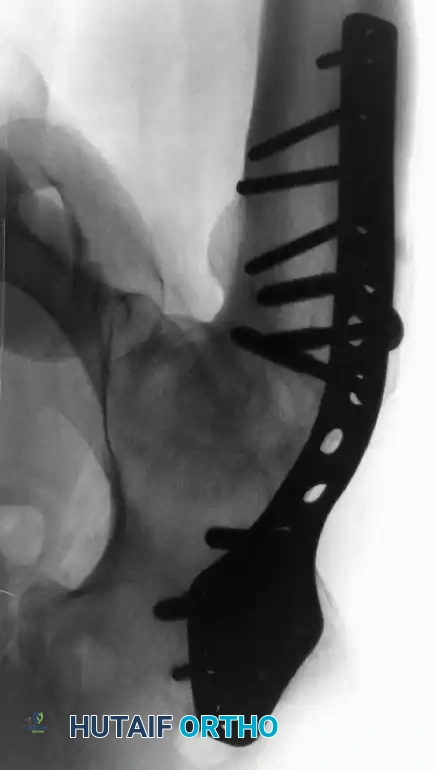

Arthrodesis with Cobra Plate Fixation

Developed by Schneider and modified by Murrell and Fitch, the cobra-head plate provides exceptionally rigid internal fixation. Crucially, this technique involves a greater trochanteric osteotomy to preserve the abductor mechanism, facilitating future conversion to a THA. It also utilizes a medial displacement osteotomy of the pelvis to improve biomechanics.

Surgical Technique 3-15:

* Positioning: Place the patient supine with a sandbag under the ipsilateral buttock. Drape to allow access to both iliac crests and ankles for alignment checks.

* Approach: Make a linear longitudinal midlateral incision along the femoral diaphysis, extending 8 cm distal to the greater trochanter. Open the fascia lata and protect the sciatic nerve.

* Trochanteric Osteotomy: Incise the vastus lateralis origin. Use an oscillating saw to perform a greater trochanteric osteotomy, ensuring the proximal fragment retains the insertion of the gluteus medius and minimus. Elevate this fragment superiorly and pin it temporarily to the iliac wing.

Fig. 3-35 (A-F): Hip arthrodesis with cobra plate fixation. Note the trochanteric osteotomy and transverse innominate osteotomy.

- Innominate Osteotomy: Perform a superior hip capsulotomy. Make a transverse innominate osteotomy between the iliopectineal eminence and the sciatic notch. Remove a 0.5-cm wafer of bone from the superior femoral head.

- Medial Displacement: Displace the distal hemipelvic fragment and proximal femur medially by 100% of the thickness of the innominate bone. This medialization reduces the joint reaction force.

- Alignment: Remove the sandbag. Insert Steinmann pins into both ASIS to act as a reference plane. Position the hip in 25 degrees of flexion, neutral rotation, and neutral adduction/abduction.

- Plating and Compression: Contour a nine-hole cobra plate. Secure the proximal portion to the ilium with a 4.5-mm cortical screw. Distal to the plate, attach an AO tensioner to the lateral femur. Apply compression force across the hip joint to ensure rigid bony apposition.

- Final Fixation: Secure the plate to the femur with 4.5-mm bicortical screws. Reattach the greater trochanter over the plate using a 4.5-mm cortical screw and washer.

Fig. 3-35 (G): Final radiographic and diagrammatic appearance of the cobra plate construct with reattached greater trochanter.